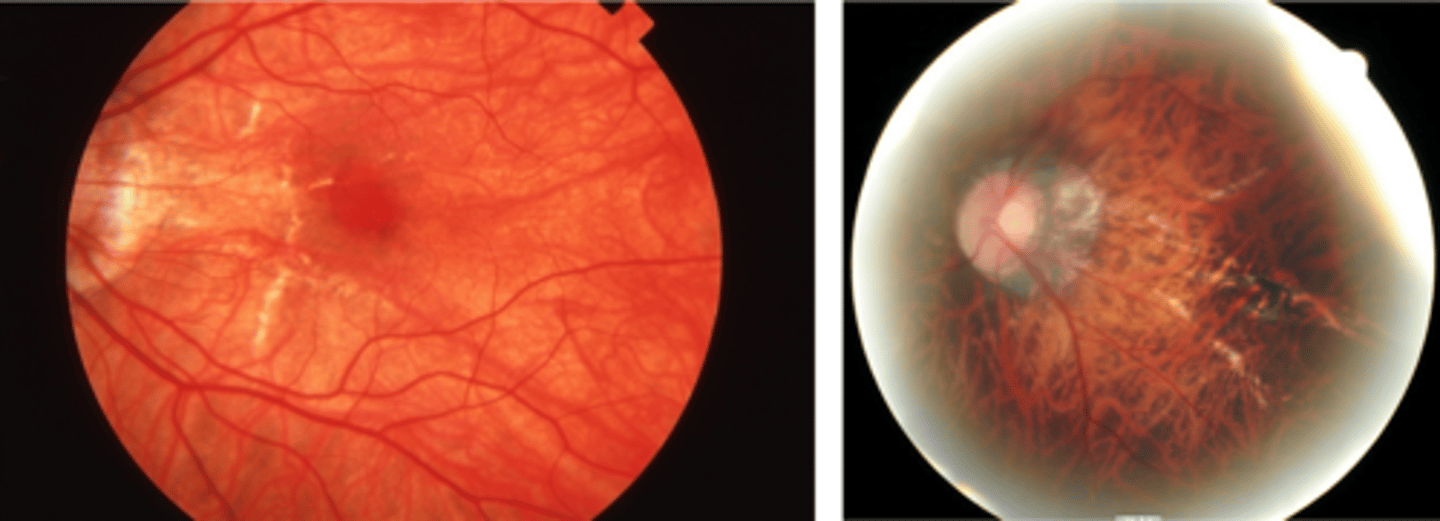

What is choroidal rupture and what causes it?

break in Bruch's membrane secondary to eye trauma (can be longstanding)

How does choroidal rupture appear on fundoscopy?

curvilinear or crescent-shaped streak, sometimes concentric to ONH

+/- subretinal /subRPE hemorrhage (acute)

Bruch's/Choriocapillaris/RPE damage

overlying neurosensory retina is intact

+/- RPE hyperplasia (chronic)

+/- CNV over time

What are the symptoms of choroidal rupture?

asymptomatic if macula avoided

absolute scotoma if macula affected

How does choroidal rupture appear on OCT here?

loss of RPE continuity at site of rupture = inner choroid atrophy

How does choroidal rupture appear on OCT here?

RPE disruption

+/- hemorrhage

How does choroidal rupture appear on FAF?

hypoAF where RPE is atrophied

How do we manage choroidal rupture?

monitor q12 mos

monitor with at-home Amsler